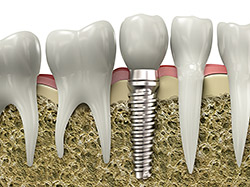

An implant is a synthetic tooth root in the shape of a post that is surgically placed into the jawbone. The “root” is usually made of titanium: the same material used in many replacement hips and knees, and a metal that is well-suited to pairing with human bone. A replacement tooth is then fixed to the post. The tooth can be either permanently attached or removable. Permanent teeth are more stable and feel more like natural teeth.

Implants are versatile. If you are only missing one tooth, one implant plus one replacement tooth will do the trick. If you are missing several teeth in a row, a few strategically placed implants can support a permanent bridge (a set of replacement teeth). Similarly, if you have lost all of your teeth, a full bridge or full denture can be permanently fixed in your mouth with a strategic number of implants.